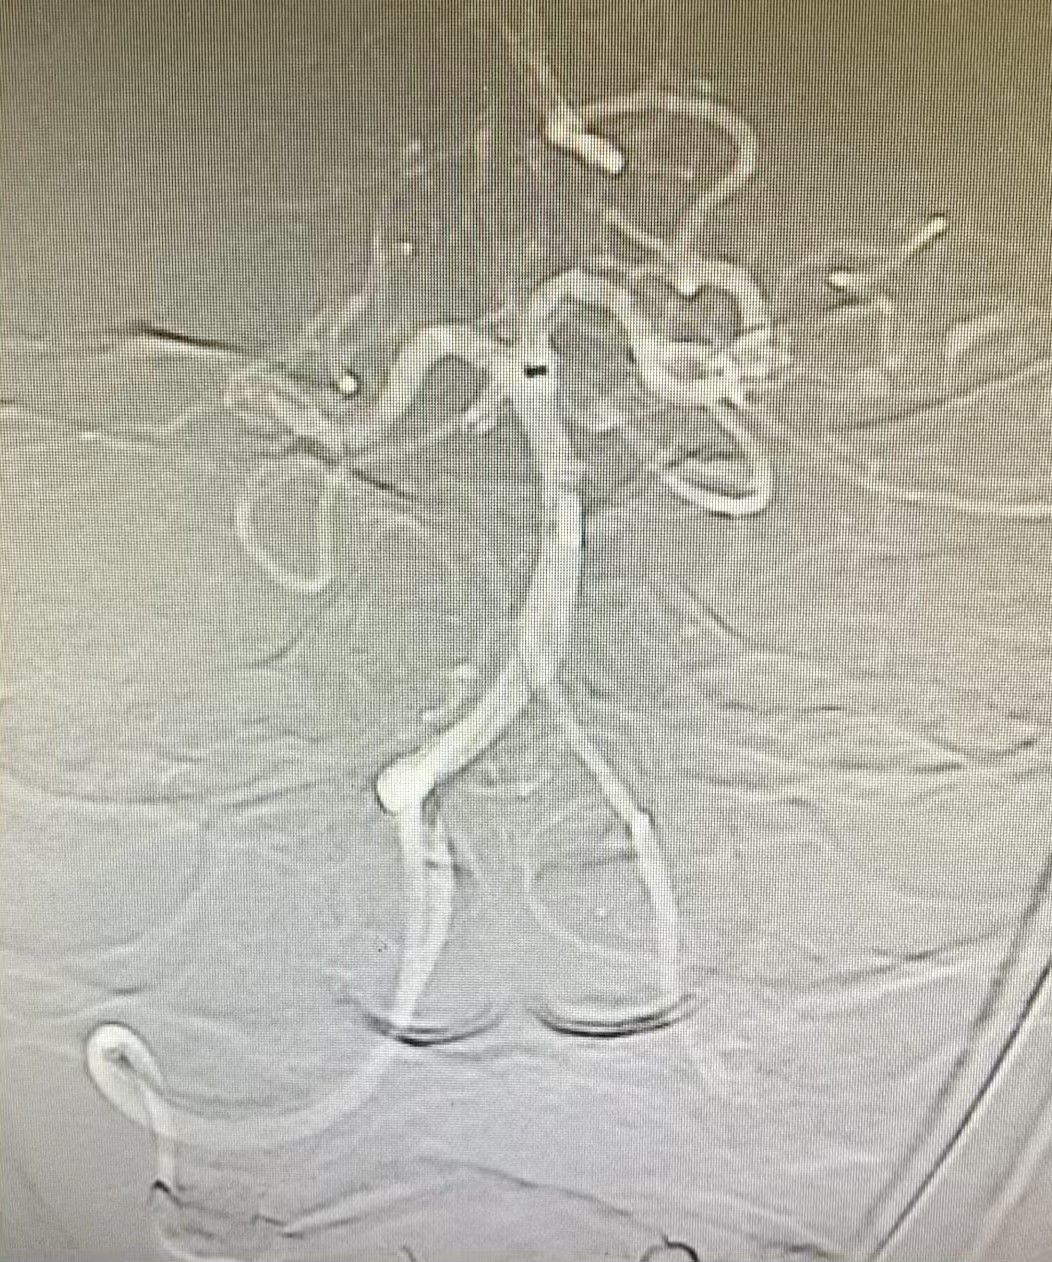

立即快速建立手术通道,采取导管“裸奔”技术送入闭塞血管,抵近血栓,采取ADAPT技术,成功将血栓抽出,血管开通,血流完全恢复正常。(图4、图5)

图5:血管完全开通,血流恢复